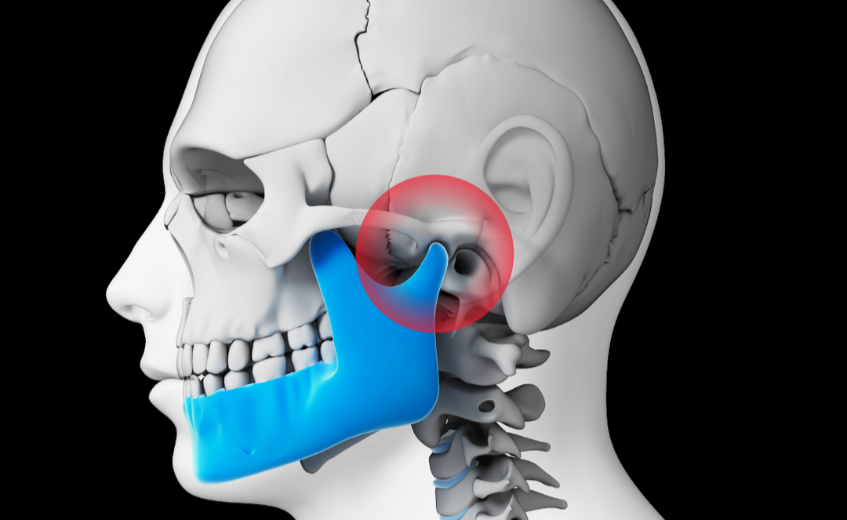

Διαταραχές στην Κροταφογναθική Άρθρωση (TMJ), γράφει η Βαρυτημίδου Φανή, PT,OMT cand.

Η Κροταφογναθική άρθρωση (TMJ) βρίσκεται σε κάθε πλευρά του κεφαλιού μπροστά από το αφτί σας. Λειτουργεί σαν συρόμενος μεντεσές, συνδέοντας το οστό της γνάθου με το κρανίο σας. Έχετε μία άρθρωση σε κάθε πλευρά της γνάθου. Οι διαταραχές της Κροταφογναθικής μπορεί να προκαλέσουν πόνο στην άρθρωση,...